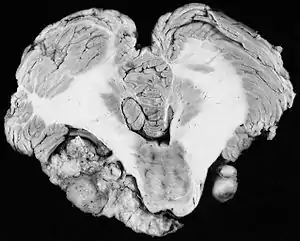

Vestibular schwannomas (VS) develop from an overproduction of non-neuronal glial (Schwann) cells that support and protect the vestibular (balance) portion of the vestibulocochlear nerve (cranial nerve VIII). VS are slow-growing, benign and non-invasive. Progression to malignancy is extremely rare.[15] They normally develop gradually over a period of years, expanding at their site of origin roughly 1–2 mm each year; however, up to 50% of such tumors do not grow at all, at least for many years after diagnosis. Tumor growth may be erratic, alternating between periods of relative dormancy or very slow growth and rapid growth. Tumors are typically described as small (less than 1.5 cm (0.59 in)), medium (1.5 to 2.5 cm (0.59 to 0.98 in)), large (2.5 to 4 cm (0.98 to 1.6 in)),[16] or giant (greater than 4 cm (1.6 in)). Tumors are described by a combination of their location and size. An intracanalicular tumor is small and in the internal auditory canal. A cisternal tumor extends outside the auditory canal. A compressive tumor infringes upon the cerebellum or brainstem. Very large tumors may obstruct cerebrospinal fluid drainage.

As intracanalicular tumors grow, they tend to expand into the cerebellopontine angle (CPA), leading to their characteristic "ice-cream-cone like" appearance on a radiograph. When the tumor expands extracanalicularly, the growth rate often increases, since it is no longer confined by the bony auditory canal. As the schwannoma expands into the CPA, it may infringe on cranial nerve V (controls facial sensation, chewing and swallowing) and cranial nerve VII (controls facial expression and taste). Cranial nerve VIII, along with these two nerves, also passes through the CPA, so more serious or complete hearing loss and episodes of vertigo may occur as the tumor infringes on it there.